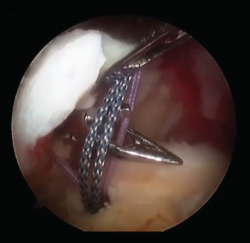

Las roturas que sí se deben reparar son las que presentan un grado de artrosis moderada(9) y aquellas con una delaminación del margen de la rotura (Figura 2). Últimamente, también se está considerando que los pacientes con factores específicos de mal pronóstico (tabaquismo, obesidad, edad, pobre calidad del tejido tendinoso…) son susceptibles de realizar una reparación de la rotura del manguito rotador, ya que no se ha demostrado suficiente evidencia en cuanto a que sean factores determinantes en el resultado funcional final(10). Igualmente, se ha demostrado que factores como la mejora del dolor pueden ser más importantes en cuanto a la buena evolución de una reparación del manguito rotador, independientemente de los factores específicos clásicos(11).

Figura 2. Rotura masiva delaminada de supraespinoso e infraespinoso.